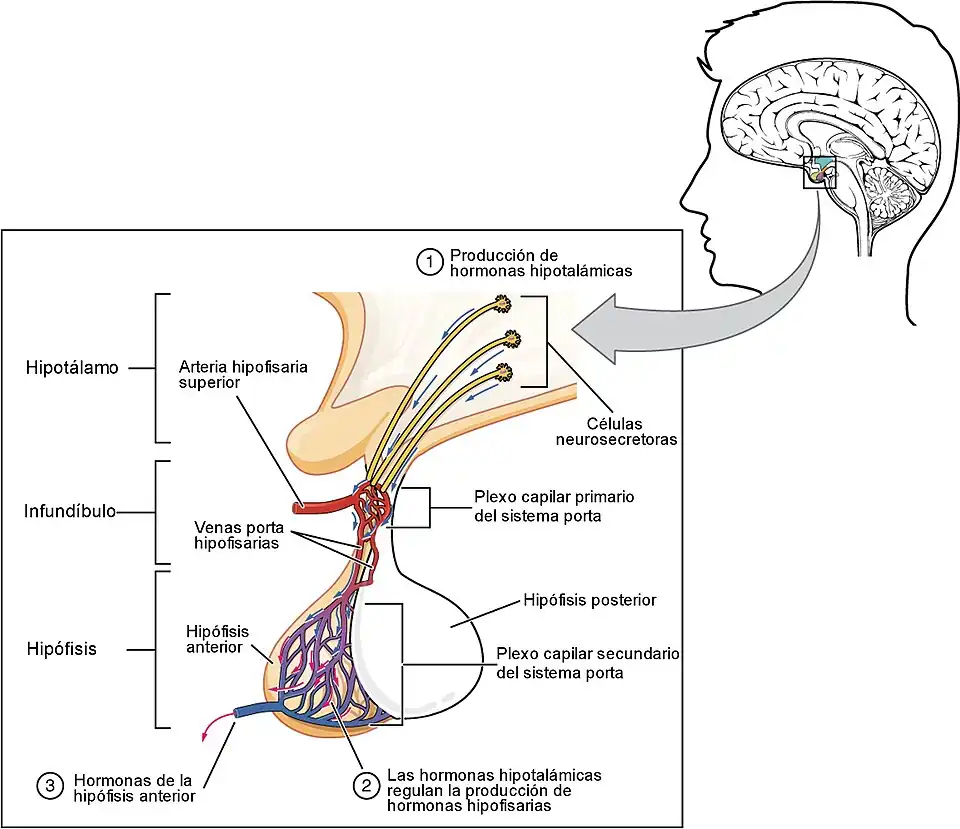

En la morfogénesis, el suelo del hipotálamo forma el infundíbulo, una evaginación digitiforme y hueca, a partir de la que se desarrollan dos estructuras: la neurohipófisis y la eminencia media. Esta última es una zona de contacto neurohemático, que forma una interfaz funcional entre el hipotálamo y el lóbulo anterior de la hipófisis.[5]

Las conexiones vasculares entre hipotálamo e hipófisis se conocen como el sistema porta hipotálamo-hipófisis que comunica los lechos capilares del hipotálamo con los del lóbulo anterior de la hipófisis. La irrigación de las estructuras llega de las arterias hipofisarias superior, media e inferior, ramas de la arteria carótida interna.[10]

- Otras 6 hormonas diferentes, las hormonas liberadoras e inhibidoras, antes llamadas "factores hipotalámicos", "factores liberadores" o "factores hipofisotrópicos" son secretados por las neuronas parvocelulares del hipotálamo y actúan sobre la hipófisis anterior (adenohipófisis), estimulando o inhibiendo su producción de hormonas hipofisarias.

Las neuronas parvocelulares o parvicelulares liberan hormonas peptídicas denominadas factores hipofisotrópicos en el plexo primario capilar de la eminencia media. A través de esta circulación porta son llevadas a la adenohipófisis para estimular la secreción de otras hormonas (hormonas hipofisarias). Ejemplos de estas hormonas hipofisiotrópicas son la GhRH (hormona estimuladora del crecimiento), TRH (hormona liberadora de tirotropina) y GnRH (hormona liberadora de gonadotrofina).